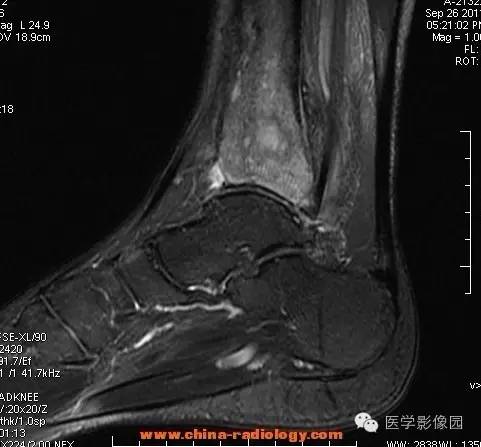

影像学表现:胫骨中下段干骺端不未规则形长T1长T2信号,T2WI见不完整环形稍低信号影,T2脂肪抑制低信号更明显,并见胫骨下段及踝关节后外侧软组织呈弥漫稍高信号,增强明显不均匀强化,增强见低信号环内有环形强化影。

影像学表现:表现为长骨干骺端有椭圆形密度减低区,边缘有清晰的骨质硬化,病变与邻近正常骨髓腔境界清楚。MRI上T1WI呈低信号,少数呈等信号,T2WI多为混杂高信号,增强扫描可见环状强化,强化的脓肿壁薄而均匀。